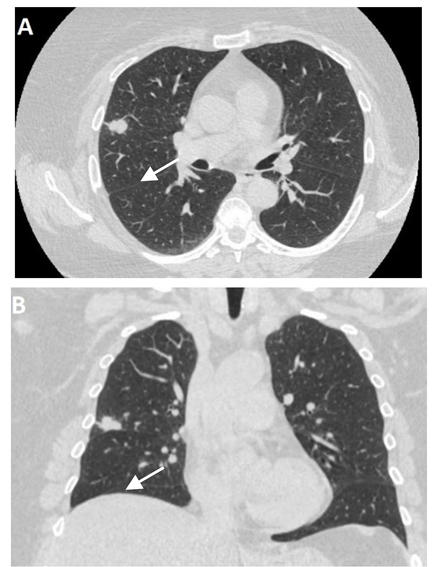

Even though X-ray is non-specific to pneumonitis, it is usually the first investigation performed. During the early phases, the most common finding on chest radiograph is perivascular haziness which frequently progresses to alveolar opacities [39]. Chest radiographs can show ground-glass opacity and/or consolidation in the radiation port. Consolidation usually has a nodular appearance but can be more confluent/lobar along with the irradiated port. Findings can be seen outside the radiation port as well. Some uncommon findings are ipsilateral pleural effusion with or without adjacent atelectasis [66]. Chest radiograph can also show bilateral interstitial infiltrates mimicking heart failure or acute respiratory distress syndrome (ARDS) [69,70]. All irradiated patients usually have some degree of abnormalities in the X-rays. Some fail to show any radiographic evidence of lung injury with pneumonitis. Early features exhibiting mild opacification of vascular markings are common, with later stages showing dense opacities. A radiographic straight-line effect may indicate the direction of the radiation port along the lines of pneumonitis [39,71] (Figure 1).

Figure 1.

Chest X-ray showing radiation pneumonitis Image 1—Frontal chest X-ray showing left upper lobe mass (arrow), the patient also had a right internal jugular port placed. Image 2—Post radiation treatment frontal chest X-ray showing increasing alveolar and interstitial opacities in the left upper lobe and in the left lower lobe in a patient suspected of radiation pneumonitis.

In the event of worsening symptoms after empirical antibiotics, Chest CT may provide more insights. Interestingly, the opacification lines in both X-ray and CT conform to radiation port rather than anatomical lines of lung structure, which could be diagnostic. Identified progression outside the lung field might suggest immune-mediated lymphocytic alveolitis [72]. Various stages of presentation provide different imaging outlooks (Table 3).

During the acute exudative stage, features of ground-glass attenuation or homogeneous consolidation may be noticed. A patchy consolidation that confirms the irradiation portal is also suggestive of the early phase. A discrete consolidation that conforms to the shape of the irradiation portal is proliferative changes of irradiation [71].

A chronic fibrosis stage with features of parenchymal distortion, traction bronchiectasis, and pleural thickening resulting in volume loss and irreversible changes are noticed. Refer to Table 2.